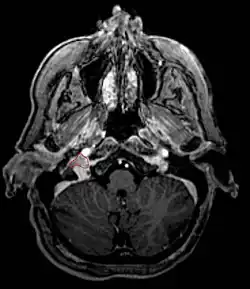

- Commonly arise from the paraganglia of the jugular bulb

- Typically invade the tympanic cavity and jugular foramen

- Can extensively invade petroclival region

- Can invade cavernous sinus above

- Can invade hypoglossal canal below

- Clinical presentation typically with tinnitus or hearing loss, but may also impact jugular foramen CNs